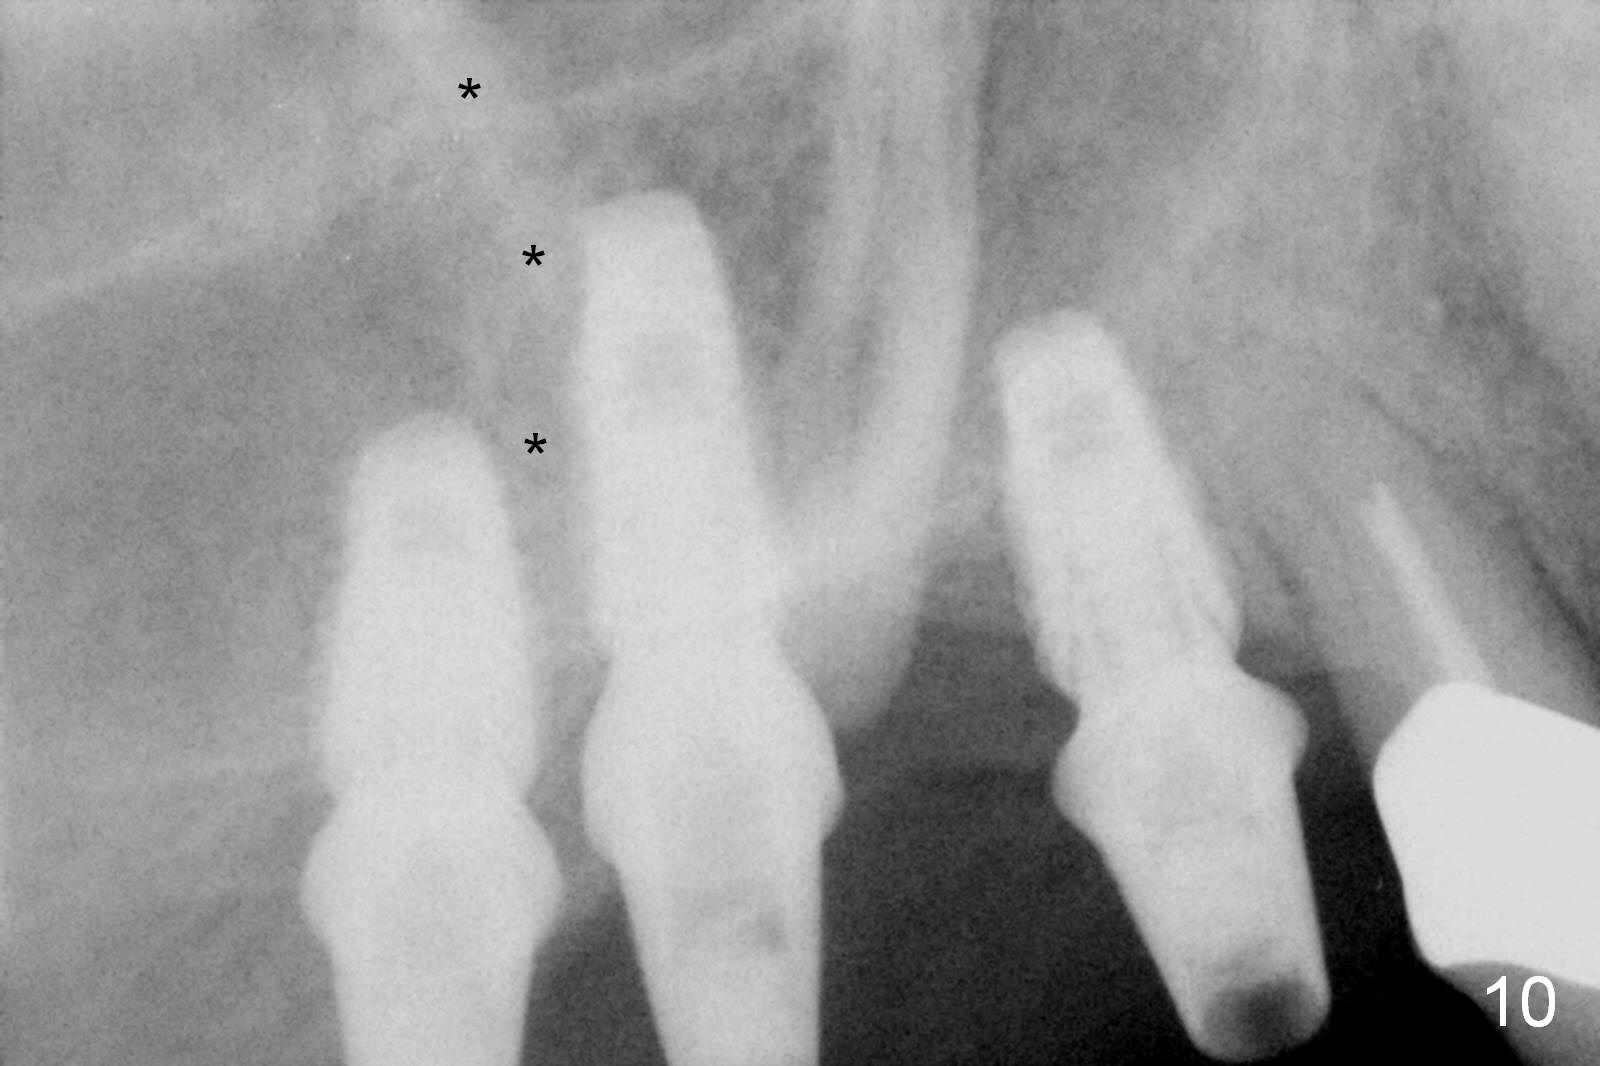

In fact, these implants seem to heal normally 2.5 months post (Fig.10). After change in abutments at #2 (from 5.5x7(4) to 4.5x5.5(5) mm) and #4 (from 5.5x7(2) to 4.5x5.5(1) mm) and torquing, impression is taken. The implant at #3 appears to be associated with the septal bone (Fig.10 *). There is no apparent bone loss 1 years 4 months post cementation (Fig.11). The patient will return for 14,15 implants.